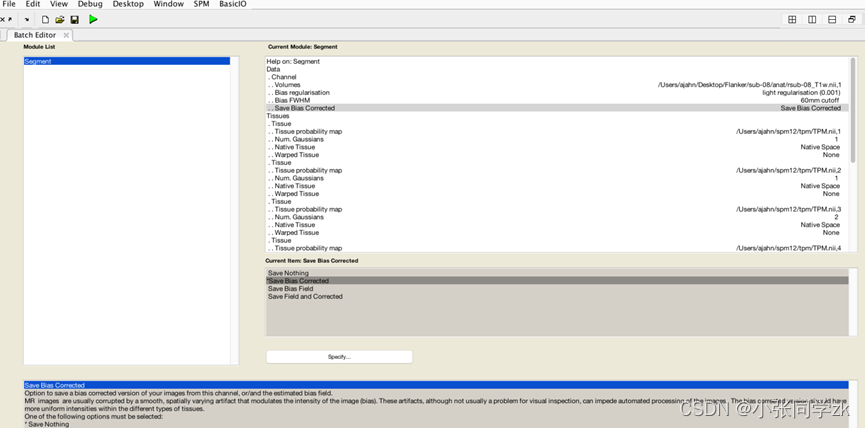

3.4 Segmentation

大脑主要由两个重要的组织组成,灰质(包含大量无髓鞘神经元)白质(有髓鞘神经元)大脑周围也充满了脑脊液,中间包含了许多脑室。

Spm中包括了6种组织,上图中从左到右依次是Grey matter; white matter; CSF; soft tissue; bone; other.将结构像的组织映射到这些组织的模板上,会增加配准的准确性。结构像不包括后面这三个组织。打开segmentation,在Volumes 中载入rsub-08_T1w.nii,将Save Bias Corrected中 的文件信息从 Save Nothing 更改为 Save Bias Corrected

在最后一栏中将 Deformation Fields 更改为 Forward

在tissue probability map这一栏中会自动载入spm12/tpm/TPM.nii